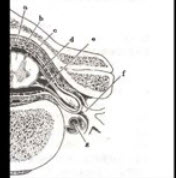

141、配伍题

如图a所示为脊髓和神经根()

如图b所示为脊髓和神经根()

如图c所示为脊髓和神经根()

如图d所示为脊髓和神经根()

如图e所示为脊髓和神经根()

A.脊神经节

B.白质

C.灰质

D.后根

E.前根